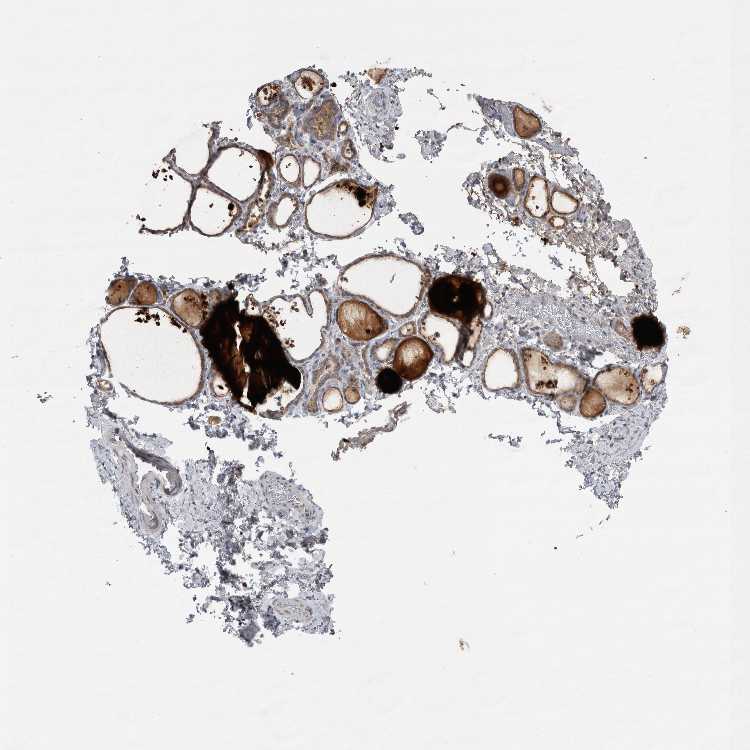

THYROID GLAND - Antibody stainingi

Antibody staining in the annotated cell types in the current human tissue is reported as not detected, low, medium, or high, based on conventional immunohistochemistry profiling in selected tissues. This score is based on the combination of the staining intensity and fraction of stained cells.

Each image is clickable and will lead to virtual microscopy that enables deeper exploration of all samples and also displays staining intensity scores, fraction scores and subcellular localization as well as patient and tissue information for each sample.

Antibody HPA018002Antibody HPA024071Antibody CAB013470

Glandular cells HighMediumMedium